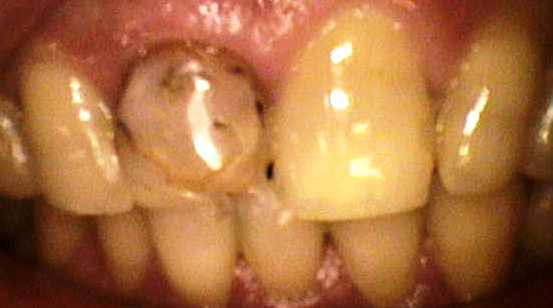

「保存修復学21」より

これは習慣的にクエン酸を飲んでいた人の口の中です。

歯が溶けて、ボロボロです![]()

おそらく、この人は常に口の中に酸がある状態だったのでしょう。

具体的には、何十分かおきにクエン酸を飲んでいたり、口の中に含ませてなかなか飲み込まなかったり、夜寝る前に飲んで歯を磨かなかったり・・・

普通は、飲食をして口の中が酸性に傾いても、しばらくすると唾液によって緩衝されてpHは中性に戻ります。

口の中が酸性の間、歯は少しずつ溶けだしますが、唾液で緩衝されると唾液中のカルシウム成分がまた歯に沈着して元に戻っていくのです![]()

この人は、唾液で緩衝される前にまた酸を摂取して、常に口の中が酸性のままだったのでしょう。